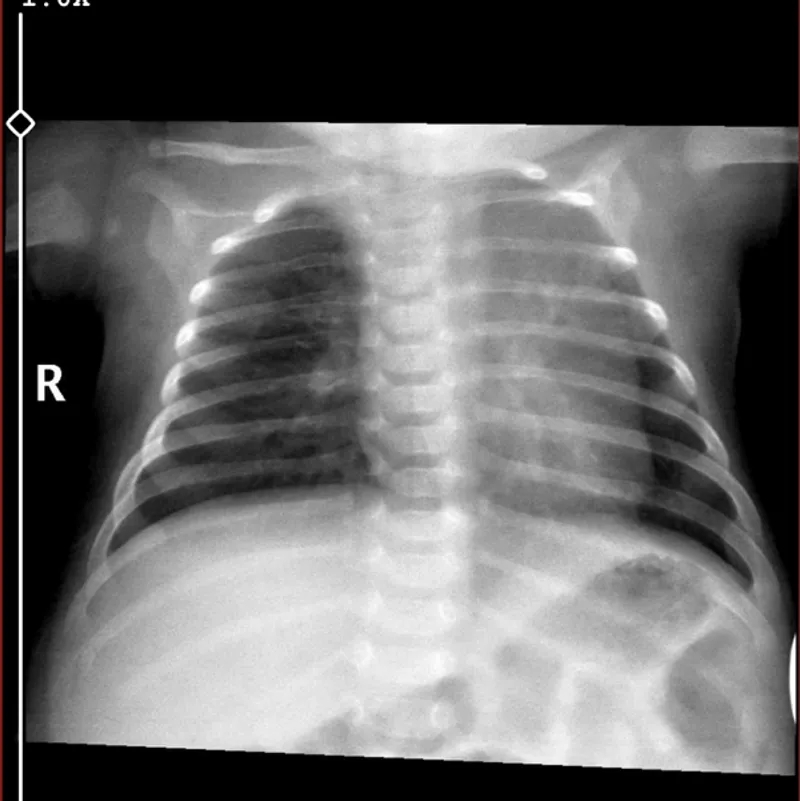

Kan testine bakılmadan akciğer röntgenine göre antibiyotik başlandı bebeğim 83 günlük röntgene göre enfeksiyon anlaşılır mı ateşi de vardı ama sadece bir kere çıktı

Bebeğinizin akciğer röntgeni enfeksiyonu gösterdiyse, doktorunuzun antibiyotik başlama kararı doğru olabilir. Akciğer röntgeni, özellikle küçük bebeklerde, enfeksiyonun yerini ve şiddetini belirlemede kan testlerinden daha etkili olabilir.

Antibiyotik kullanımı genellikle bakteriyel enfeksiyonlarda gereklidir. Eğer doktorunuz röntgen sonucuna göre enfeksiyonu tespit etmişse, antibiyotik tedavisi başlatmak mantıklıdır.

Bebeğinizin ateşi sadece bir kere çıkmış olsa bile, enfeksiyonun yayılmaması için tedavi edilmesi önemlidir.